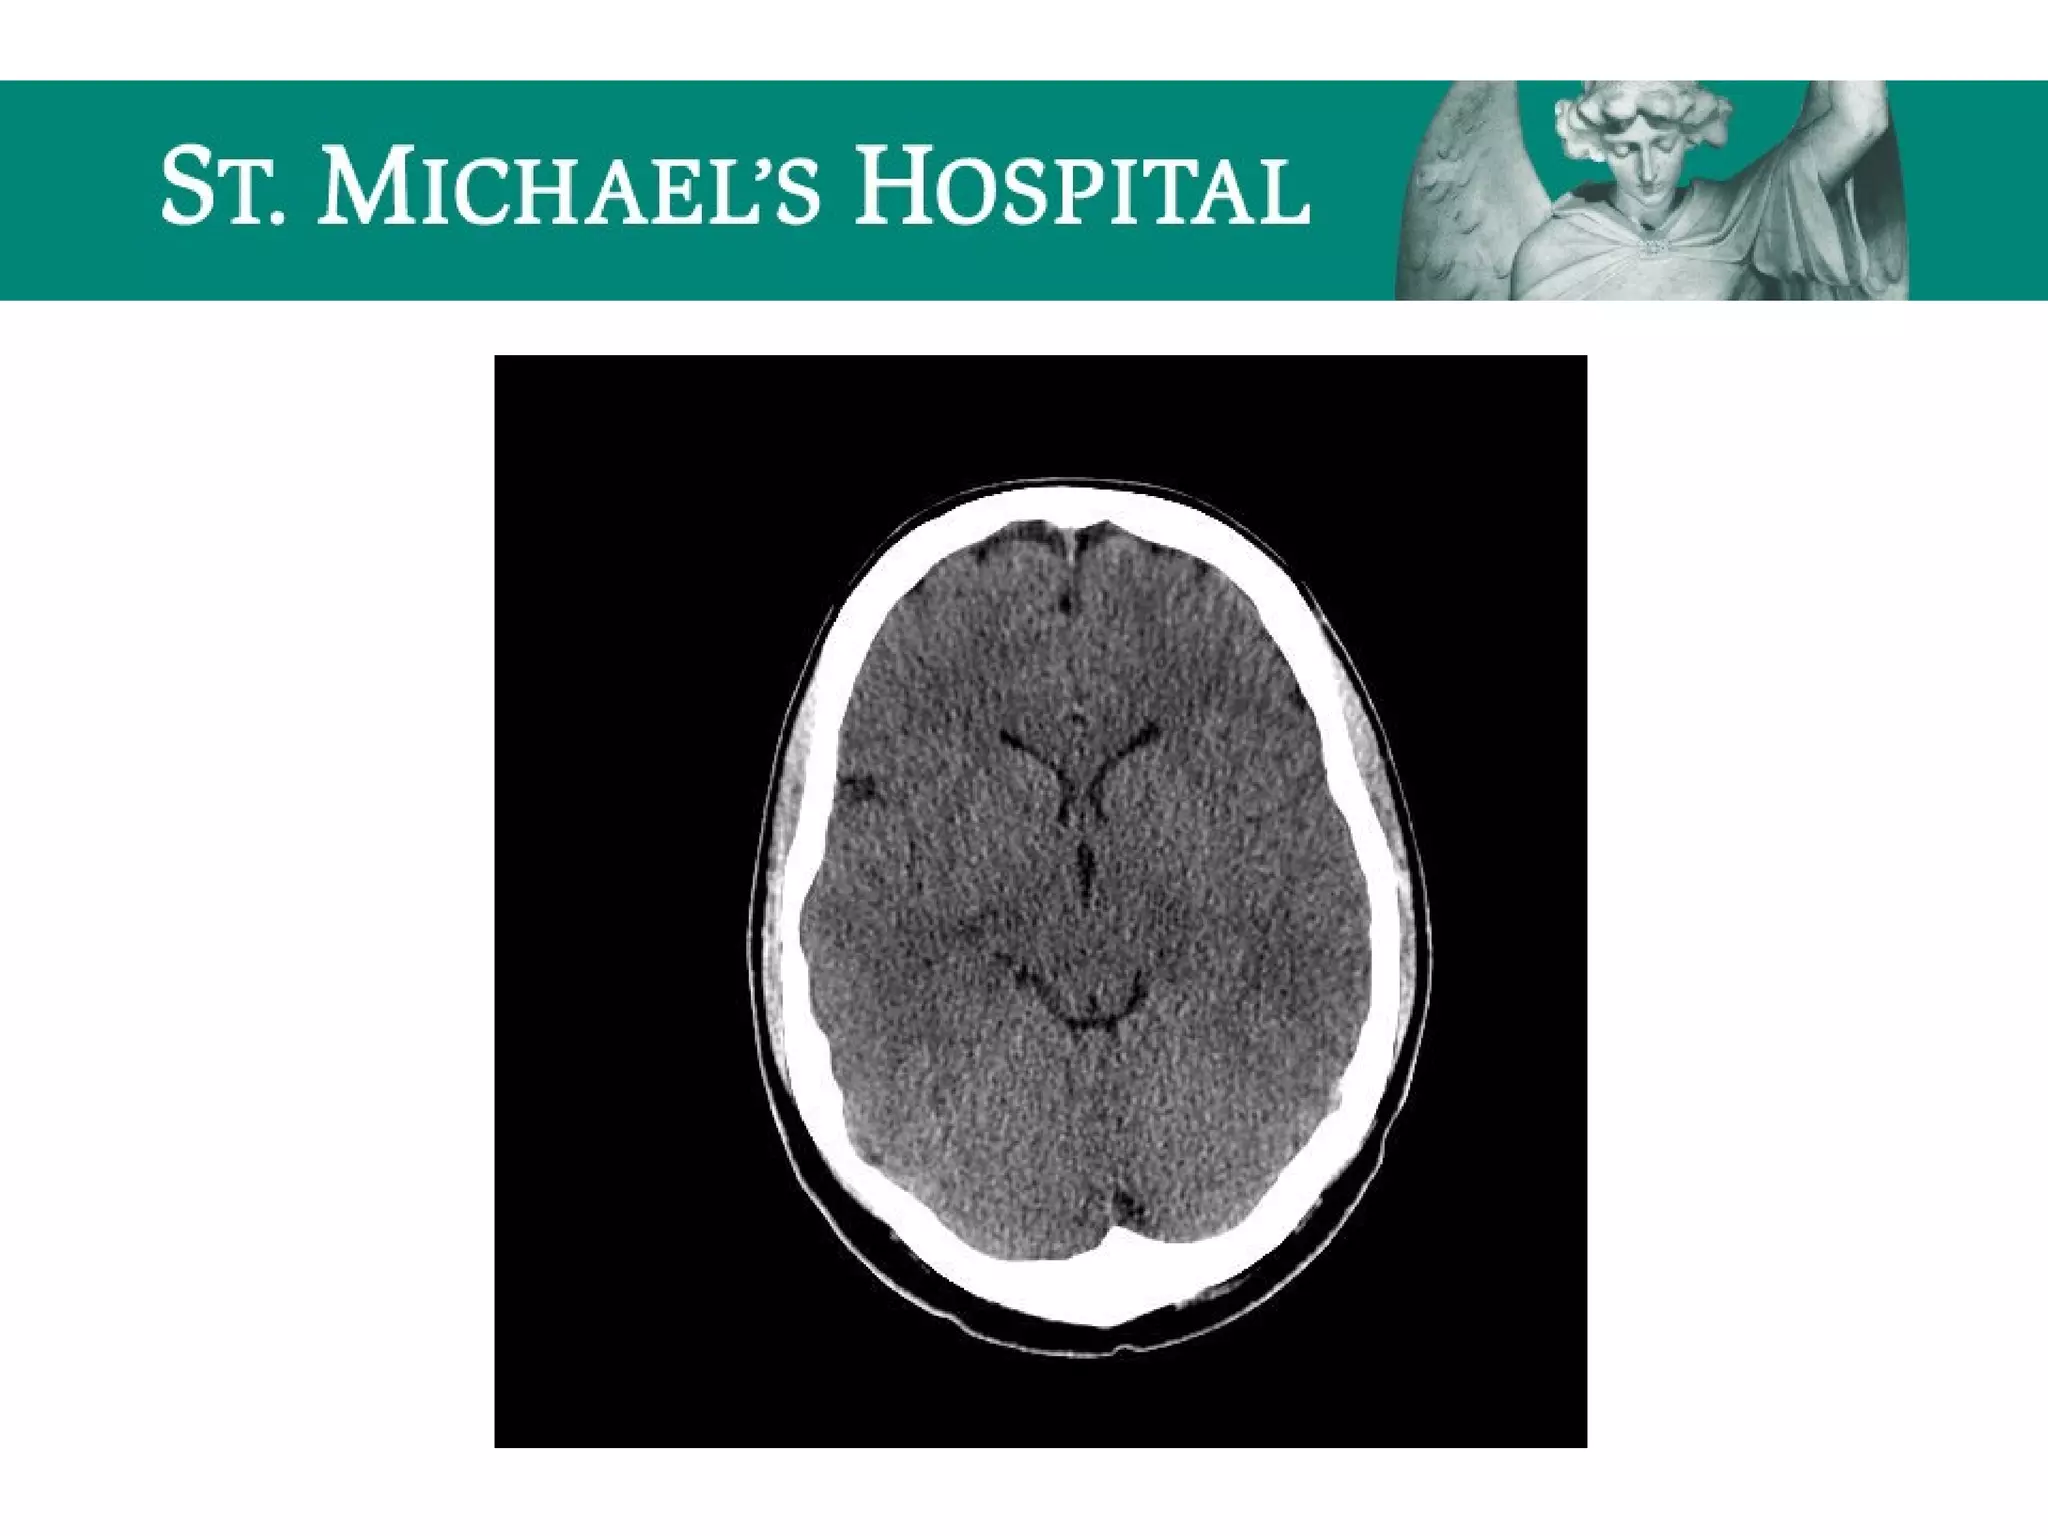

Global Cerebral Ischemia/Anoxic Brain

Injury

 Diffuse brain swelling/edema can result in:

 global loss of gray-white differentiation

 global sulcal/cisternal effacement

 pseudo-subarachnoid hemorrhage

 dense cerebellum